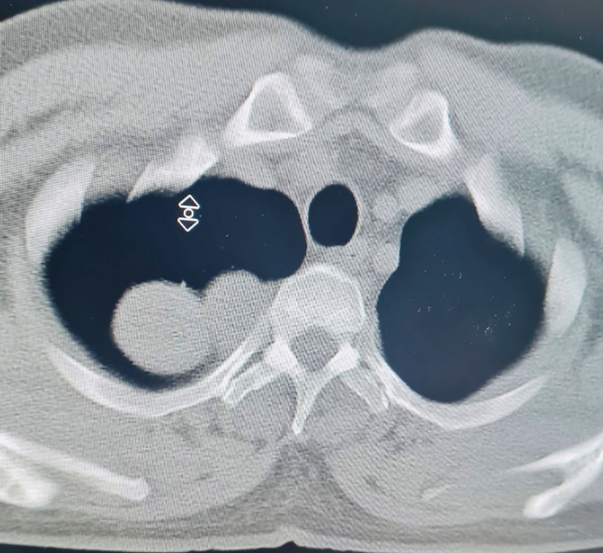

Bệnh nhân là anh Nguyễn Đức T. 40 tuổi vào viện trong tình trạng tức ngực, khó thở kéo dài, đau lưng, vai và cánh tay. Qua chụp cộng hưởng từ và cắt lớp vi tính phát hiện bệnh nhân có khối u từ trong ống sống ngực đã phát triển vào trong lồng ngực với kích thước lớn 3×4 cm. Khối u này đã phát triển vào trung thất sau ăn sát hõm đỉnh lồng ngực, đè đẩy vào bó mạch thần kinh cánh tay, đặc biệt là tĩnh mạch dưới đòn trái.

Hình ảnh khối u của bệnh nhân T. trên phim chụp cắt lớp vi tính và cộng hưởng từ